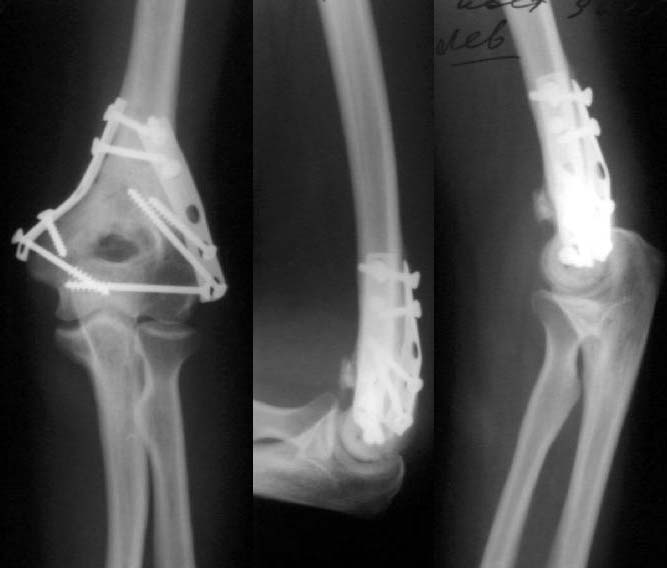

Результат в 6 месяцев

Лечение тут, видимо, должно основываться в первую очередь на открытой репозиции, поскольку возможности закрытой при таких повреждениях далеко недостаточны. Если поверхность блока состоит не просто из двух крупных фрагментов, лучше идти с отсечением локтевого отростка. Вопрос о методе фиксации более второстепенный. Можно и аппаратом. В приложении - пример лечения такого повреждения с внутренней фиксацией.

Все же открываться мы не стали. Результаты в приложении. Фронтальный снимок переделаю и пришлю еще раз. Мнения?